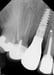

Following a GBR at the time of implant placement (Pictures 1,2,3), a buccal ridge deficiency persisted (Picture 4). Surgical uncovery of the implant to expose the cover screw revealed successful bone regeneration around the implant, but a residual lack of ridge contour (Picture 5).

Instead of using a traditional particulate graft covered with a resorbable membrane, a “flexible bone graft” sheet, DALI Flex Graft, was placed over the buccal plate to augment the buccal contour (Pictures 6 & 7). Because the graft comes hydrated, it is easy to handle and adapt to the defect location. The flap was then pulled over the graft and adapted around the healing abutment (Picture 8).